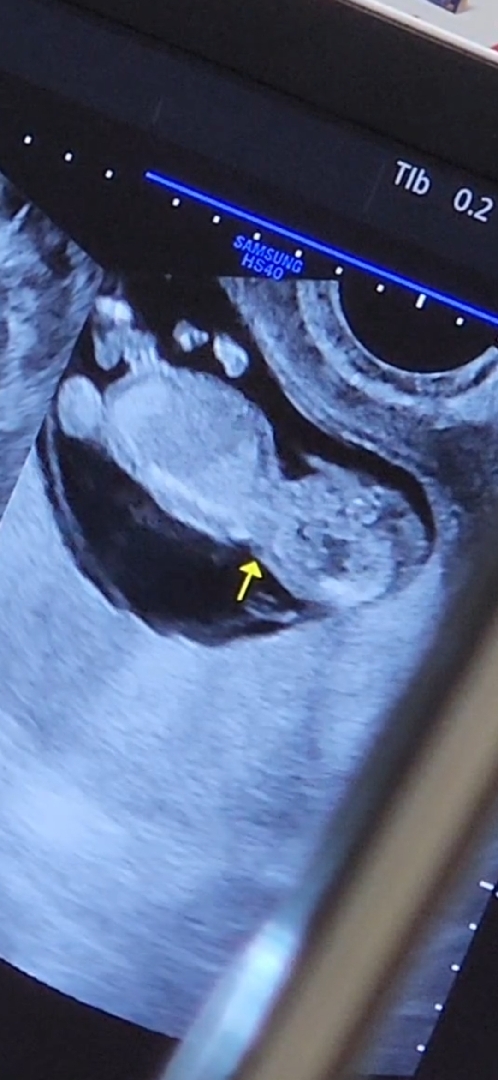

딸인지 아들인지 너무 궁금해요ㅎㅎ 혹시 이사진으로도 각도법 볼수있을까요??(사진이 한장만 가능해서 따로올려요ㅎㅎ)